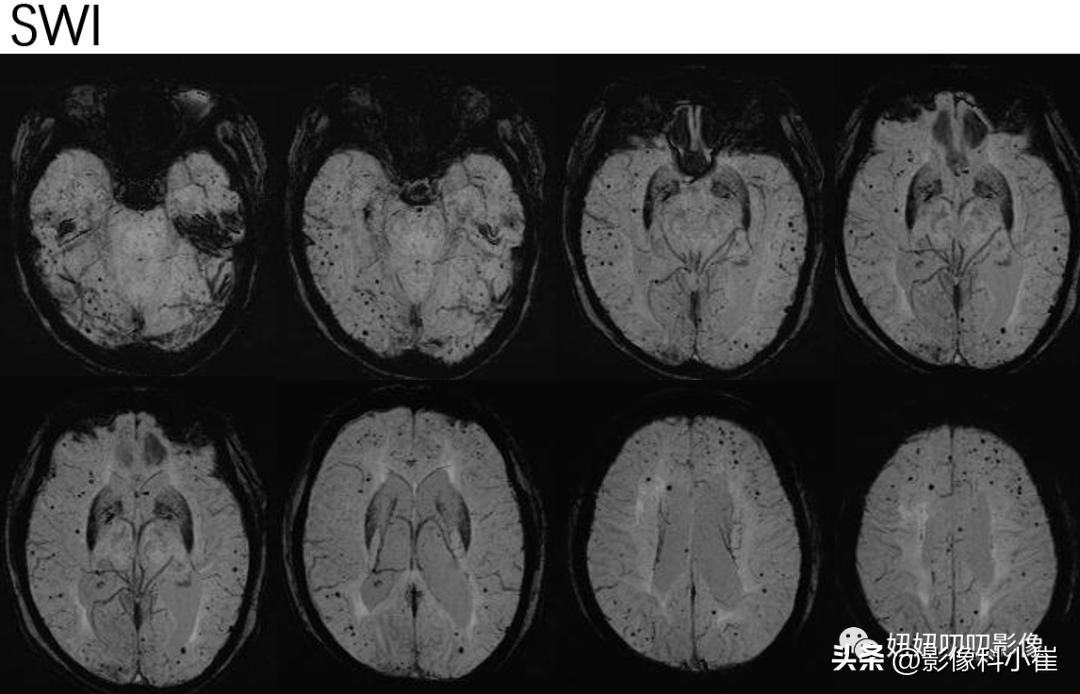

SWI:双侧小脑半球、大脑半球见多发大小不等斑点状低信号,病变多位于皮质区及皮髓质交界区。